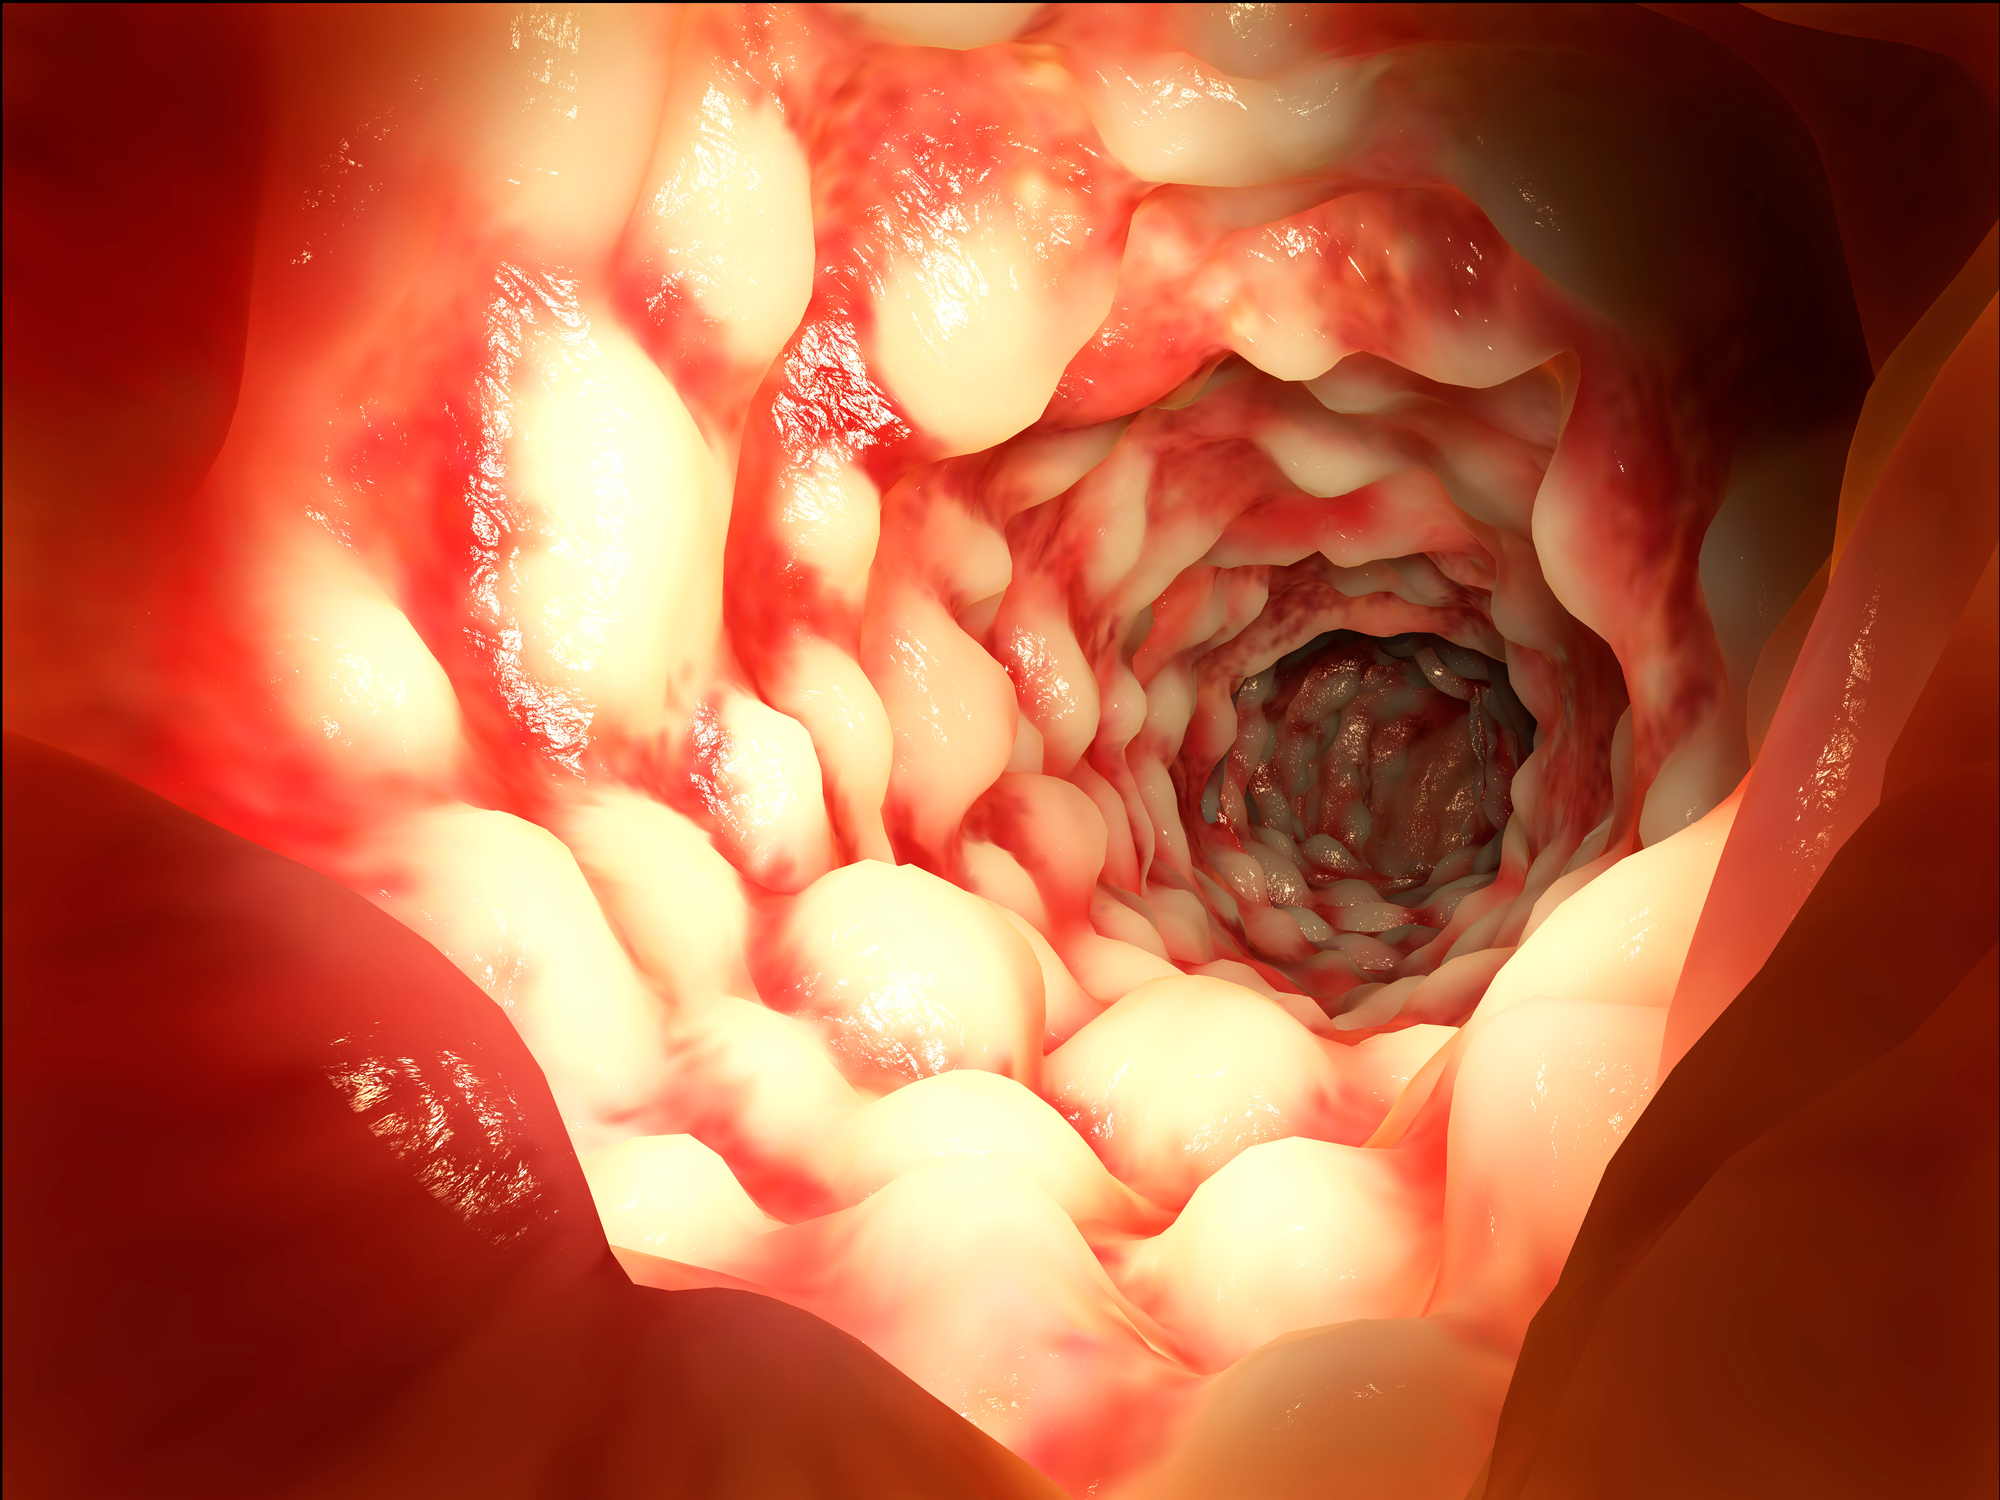

This week’s health news roundup includes recent stories about celiac disease, ulcerative colitis, rheumatoid arthritis, fibromyalgia, and inflammatory bowel disease (IBD). This week, we discussed the benefits of going gluten-free in celiac disease, possible treatment for ulcerative colitis, risk of cancer in rheumatoid arthritis, positive impact of aquatic aerobics on fibromyalgia patients, and the problem ...click here to read more